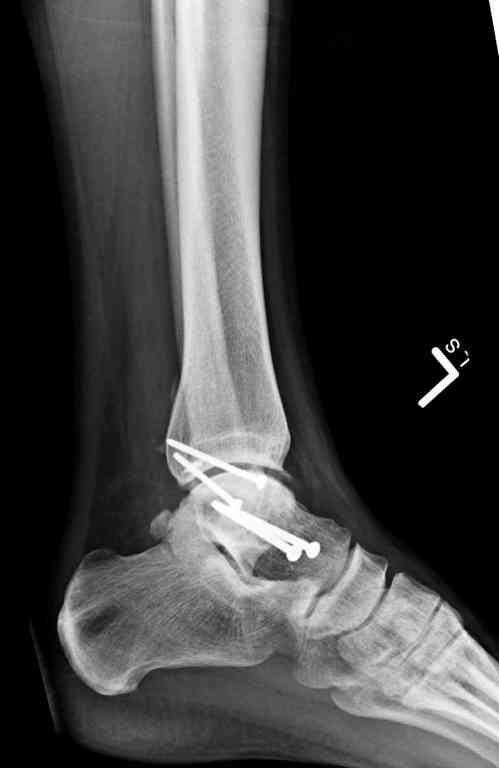

Переломовывих тарана с повреждением медиальной стороны. Через 4 часа после поступления проведена репозиция и фиксация тарана после Irrigation&Debridment. Частичное несращение медиальной лодыжки не беспокоит, вернулся к активному образу жизни. Полная нагрузка разрешена через 11 недель. Финальные снимки через 11 месяцев.